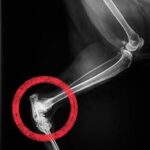

検査の結果 骨端軟骨形成と診断がつきました。

軟骨形成

正常

特にレントゲン検査では、骨や関節の状態を詳しく確認することができ、

「どの関節に」「どの程度の変化が起きているのか」を正確に把握できます。